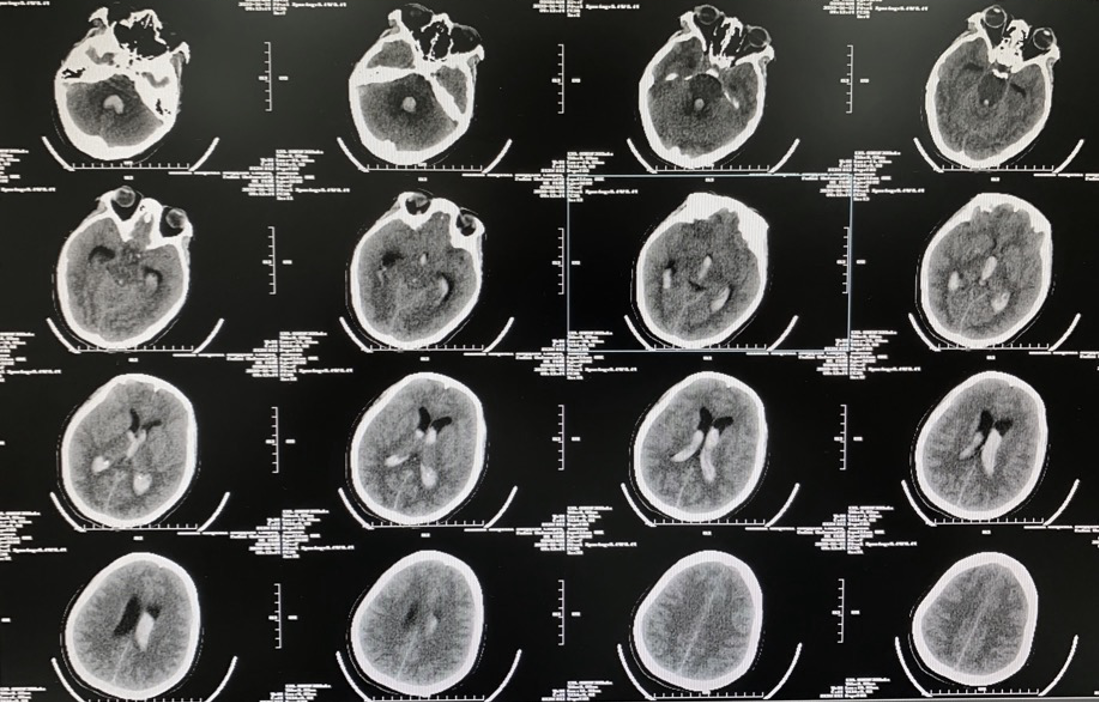

术后CT